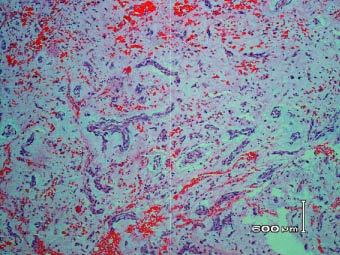

Postmortem histological examination of the liver showed complete loss of the normal hepatic architecture and massive hepatocellular necrosis, associated with marked portal and periportal cholestasis (Fig. 13.13), accompanied by collapse of the reticulin framework (Fig. 13.14). There was moderate, chronic portal inflammation, with occasional, relative preservation of a few periportal hepatocytes in some areas. Perivenular fibrosis was noted, but veno-occlusive disease and hepatic cirrhosis were absent. No Mallory bodies, giant mitochondria, or steatosis were observed in the residual hepatocytes. Toxicological analysis was negative.

Fig. 13.13.

Case #5: Massive hepatocellular necrosis with marked periportal cholestasis (PAS ×200)